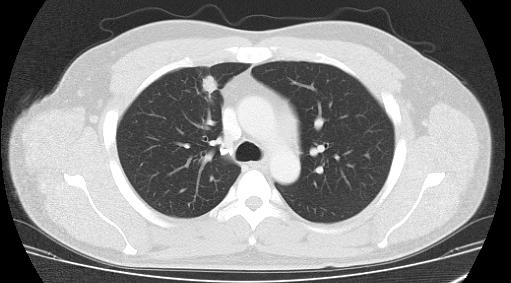

随着人们健康体检意识不断增强,临床上肺部小结节诊断越来越多,但肺部小结节大多数为良性结节,少部分为恶性。